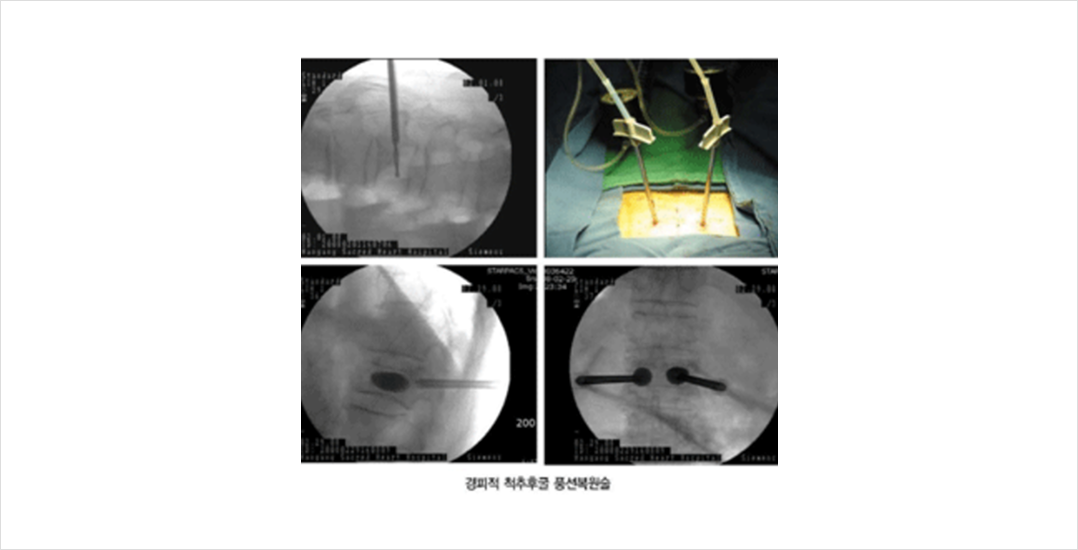

대개의 경우 보존적 치료를 하게 되며 치료 효과도 좋습니다. 골다공증 정도에 따라 1-3주 정도 절대 침상 안정을 하고 그 이후에 통증이 호전되면 척추 보조기를 착용하고 거동을 시작합니다. 대개의 경우 2-3개월 정도 지나면 골유합이 진행되면서 증상이 호전됩니다. 하지만, 3주 이후에도 증상의 호전이 없고, 80세 이상의 고령이거나, 골다공증이 심한 경우, 오래 누워 있어 합병증이 예상되는 경우 (당뇨, 심장 질환 등) 에는 조기에 거동을 시작하기 위하여 척추체 성형술을 시행하기도 합니다.

전신마취를 하지 않고 시술이 빠르고 안전하여 가장 널리 쓰이는 방법중의 하나입니다. 대부분의 경우 시술 직후부터 통증이 호전되며, 척추후굴풍선 복원술의 경우 압박 변형된 척추체의 일부를 복원할 수도 있습니다.